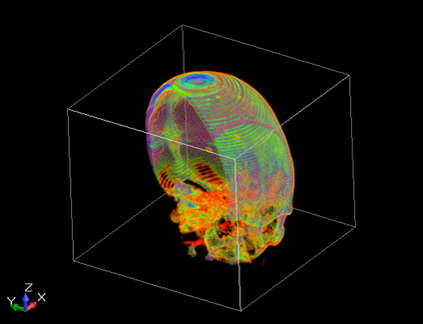

Это не абстрактная теоретическая проблема. Я сам сталкивался с ситуацией, когда при переносе программы на 64-битную систему начала проявляться ошибка, приводящая к неправильной обработке МРТ-данных. К счастью, ошибка проявляла себя очень явно: отсутствовал большой фрагмент изображения. Однако ошибка может быть не столь заметной и заключаться в неправильном отображении каких-то мелких деталей, и обнаружить её будет гораздо сложнее.